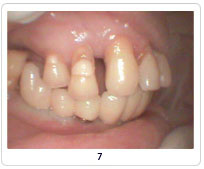

Implant Cases

Case 1   Case 2   Case 3   Case 4   Case 5   Case 6   Case 7   Case 8

Pictures Before And After Dental Implant India,Dental Implant Methods India,Types Of Materials Dental Implant Chennai India,X-ray Dental Surgery Goa India,Replacement Of Damaged Teeth Cochin India,Views Of Dental Treatment Procedure Delhi India,Dental Equipments Hyderabad India